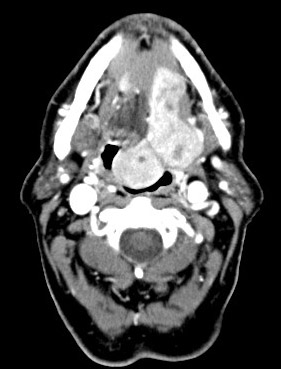

History: The patient was a 75 year-old man who presented with a

pedunculated, submucosal tumor at the base of the tongue as illustrated

in the CT scan. A fine needle aspiration was performed and

an excision was subsequently performed. The excised specimen was a 6.0 x

3.5 x 2.0 cm mass with solid cut surface that was free of cystic changes

or necrosis.

CT Scan